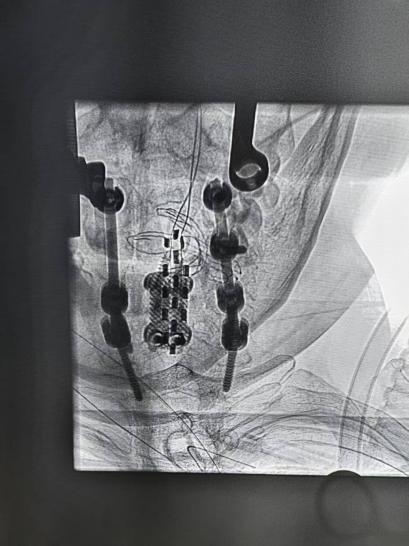

2025-04-29五院技术 | 而立之年遭遇高位截瘫?这场手术让"沉睡"神经重启

高位截瘫患者的世界是否只剩疼痛与绝望?33岁的凌先生用亲身经历给出否定答案——广州医科大学附属第五医院脑科中心团队通过一项"神经起搏"技术,用15天,让患者在瘫痪7个月后首次感受到肢体力量…